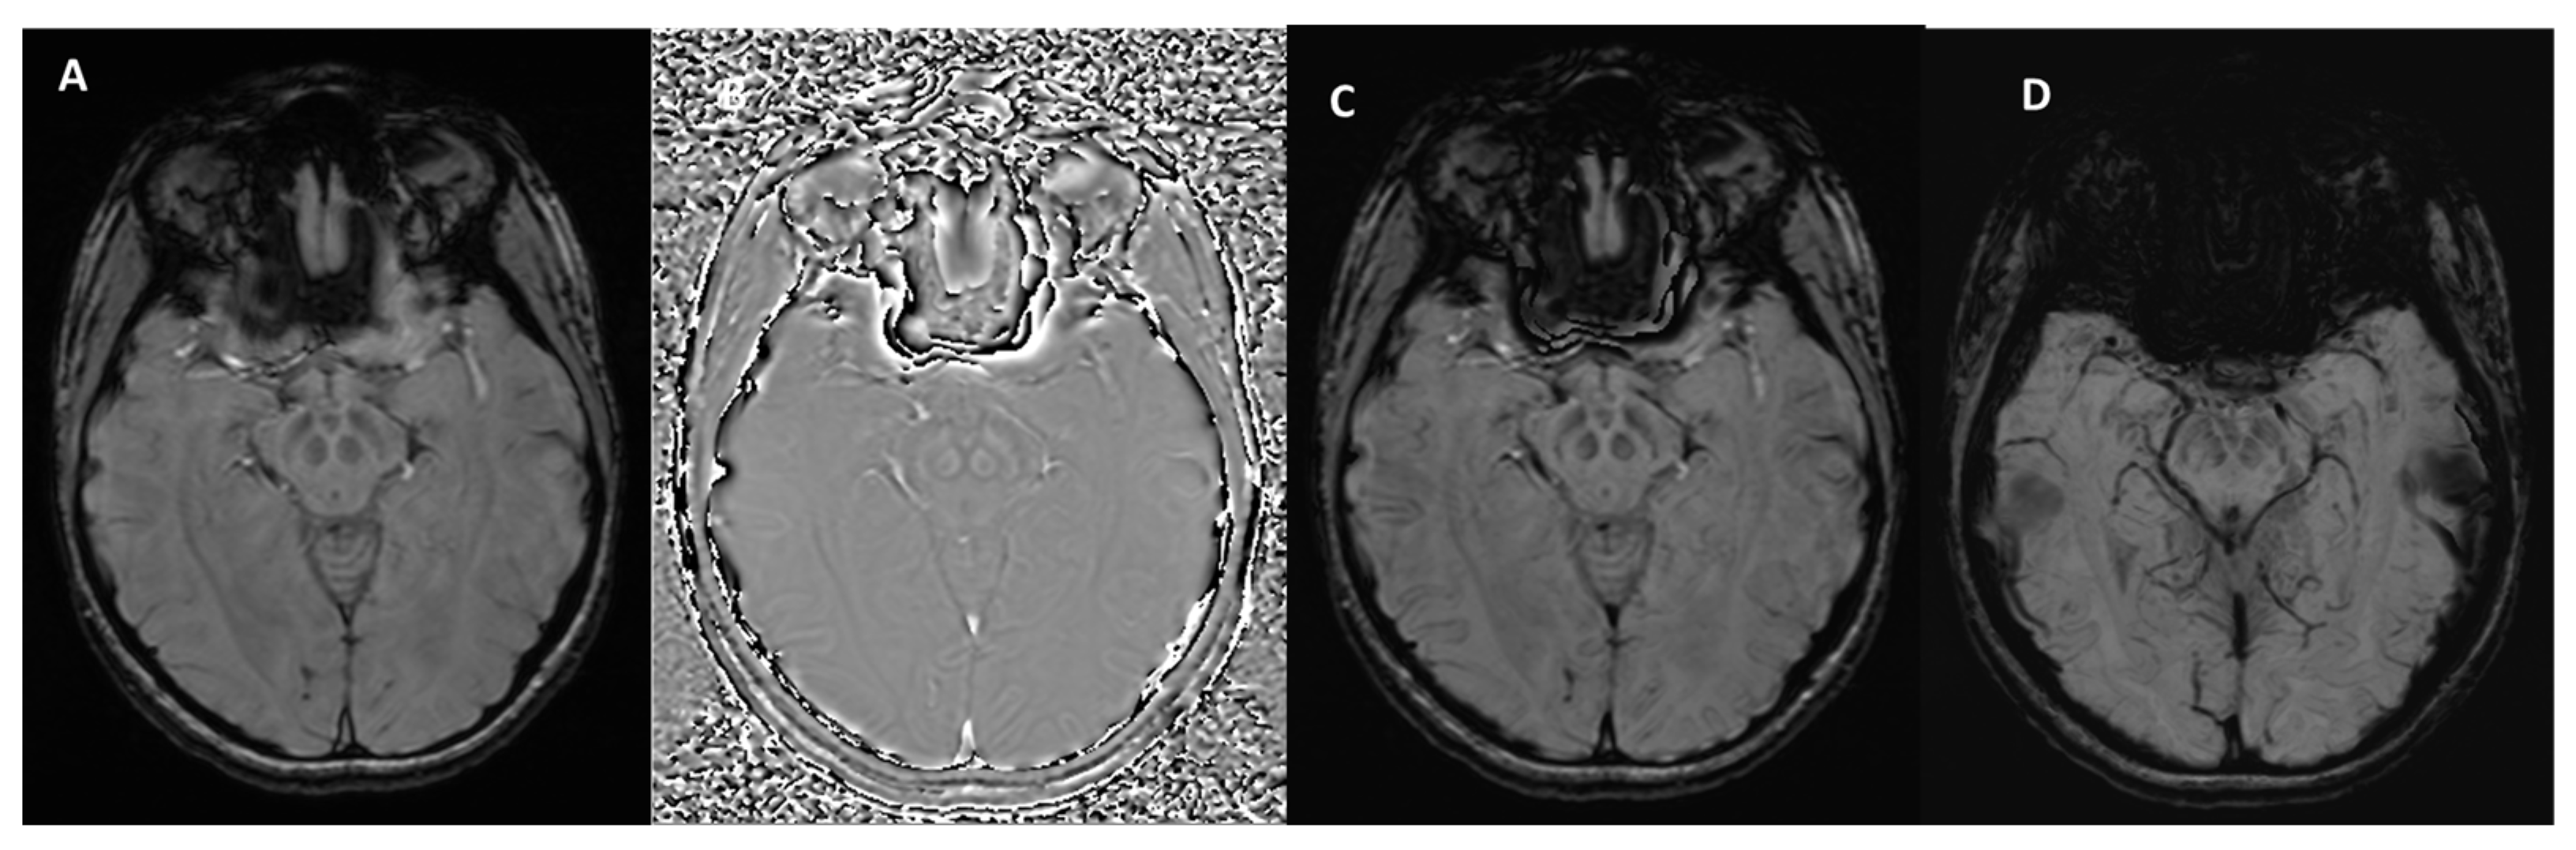

3. Technical Fundamentals of SWI

How Can Calcifications and Blood Be Differentiated on an SWI Phase Map?